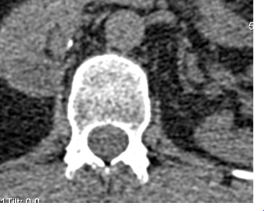

Then there is the other me on Twitter . BoariJ. Boari is the flap of bladder that was constructed twice to try to join up to my right kidney. Not for the squeamish . BoariJ tries to raise awareness, cheer the success of incredibly brilliant clinicians and patients, who despite all odds seem to be so positive so forward looking and taking the twitteri by storm. Some of the consultants I know tweet, support each other and ponder weird blurry images of god knows what bit of the urinary tract.